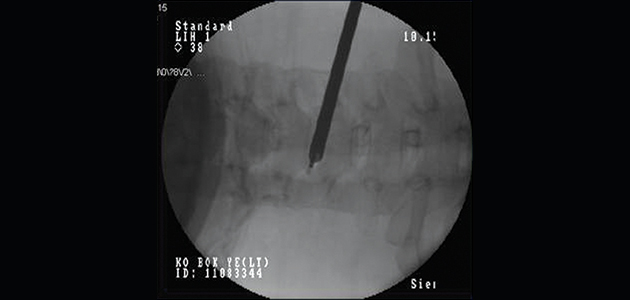

‘Percutaneous Cervical Decompression’ that selectively treats only the lesion using a 4mm diameter endoscopic tube

36-year-old male patient complaining of radiculopathy